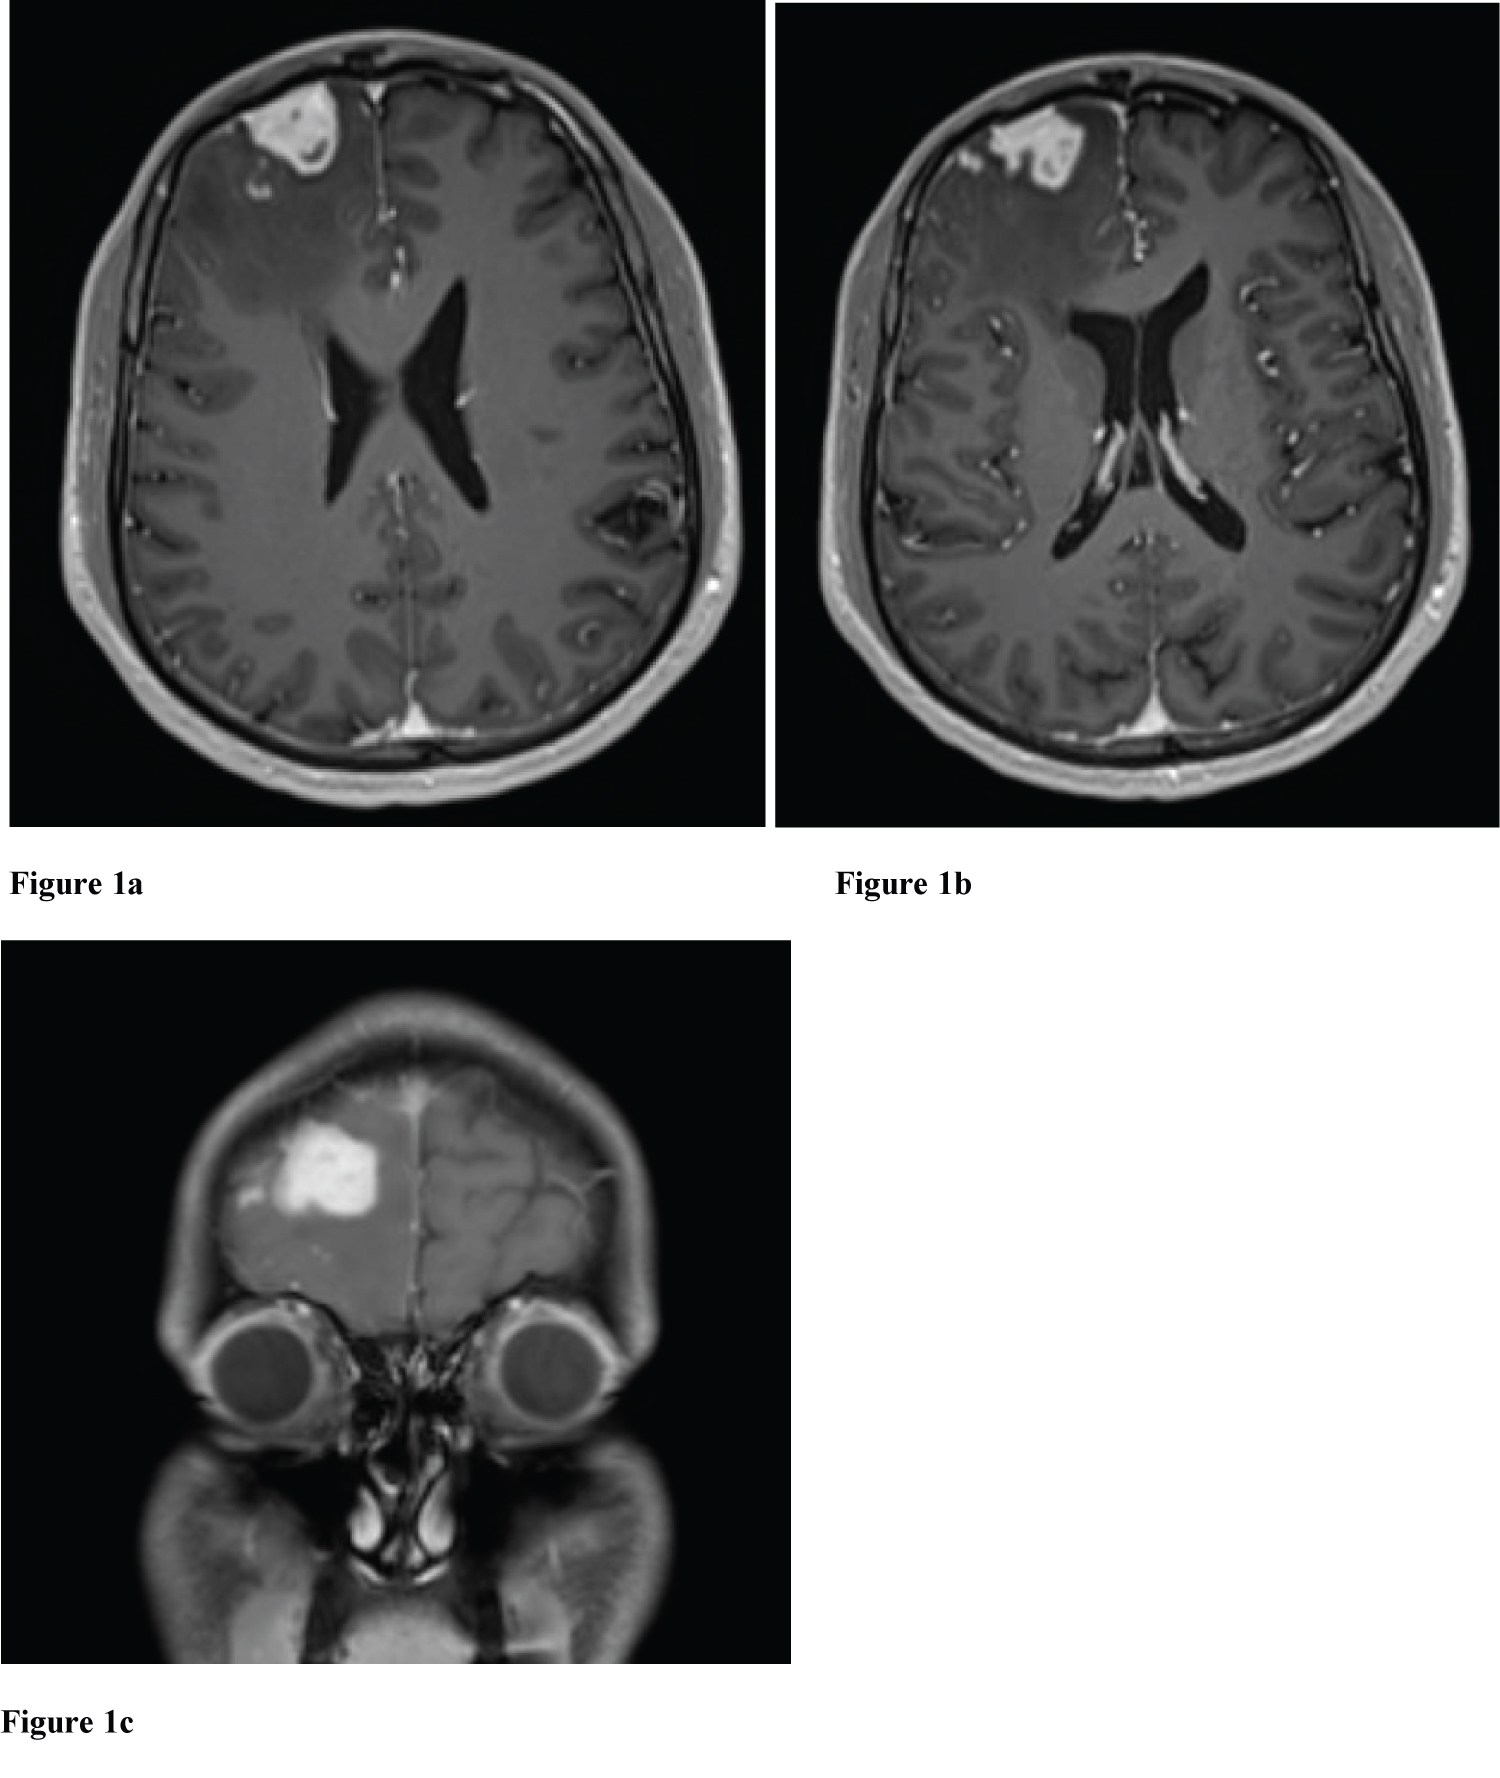

Axial non-contrast head computed tomography (CT) showed a slightly hyperdense dural-based mass in the right frontal cortex measuring 19 mm in maximal dimension with adjacent vasogenic edema in the right frontal lobe causing regional sulcal and right lateral ventricular effacement without midline shift-suggestive of possible meningioma. Chest, abdomen, and pelvis CT with contrast were negative for primary sites. Head magnetic resonance imaging (MRI) with IV (intravenous) gadolinium contrast with coronal imaging through temporal lobes was obtained. Post-gadolinium enhancement, the mass measured 20 × 24 × 20 mm in maximal dimension (Figure 1). Peripherally, the mass appeared to have a broad dural-base; however, it was more representative of an eccentrically located intra-axial lesion with isolated enhancing foci-suggestive of brain invasion. There was leptomeningeal enhancement in the adjacent frontal sulci, with vasogenic edema contributing to regional sulcal effacement and mild effacement of the frontal horn of the right lateral ventricle, without midline shift. The vasogenic edema extended into the right lateral aspect of the genu of the corpus callosum. Imaging findings were suggestive of a meningioma, with differential diagnoses including atypical meningioma with brain invasion, infectious etiology, and lymphoma.

Figure 1: (a-c) Radiology. Axial T1 MRI (a-b) and Coronal T1 MRI (c) with contrast demonstrating an enhanced dural-based mass in the right frontal cortex with adjacent vasogenic edema. Of note, isolated foci with enhancement are seen within the brain parenchyma. There is protrusion of the mass lesion, which further suggests brain invasion. View Figure 1